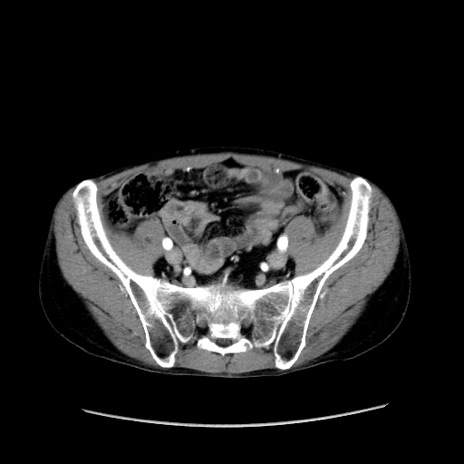

症例37(横断像)

冠状断像

【症例】40歳代 男性

【主訴】腹痛

【現病歴】4時間ほど前に電車に乗車中に臍部上より腹痛出現。徐々に増悪し起立困難となり、救急外来受診。生ものは数日食べていない。今朝お雑煮を食べた。

【身体所見】BT 36.8℃、BP 117/84mmHg、HR 91/min、SpO2 97%、苦悶様、腹部:臍上部広範囲圧痛あり、反跳痛±

【データ】WBC 8100、CRP 0.03